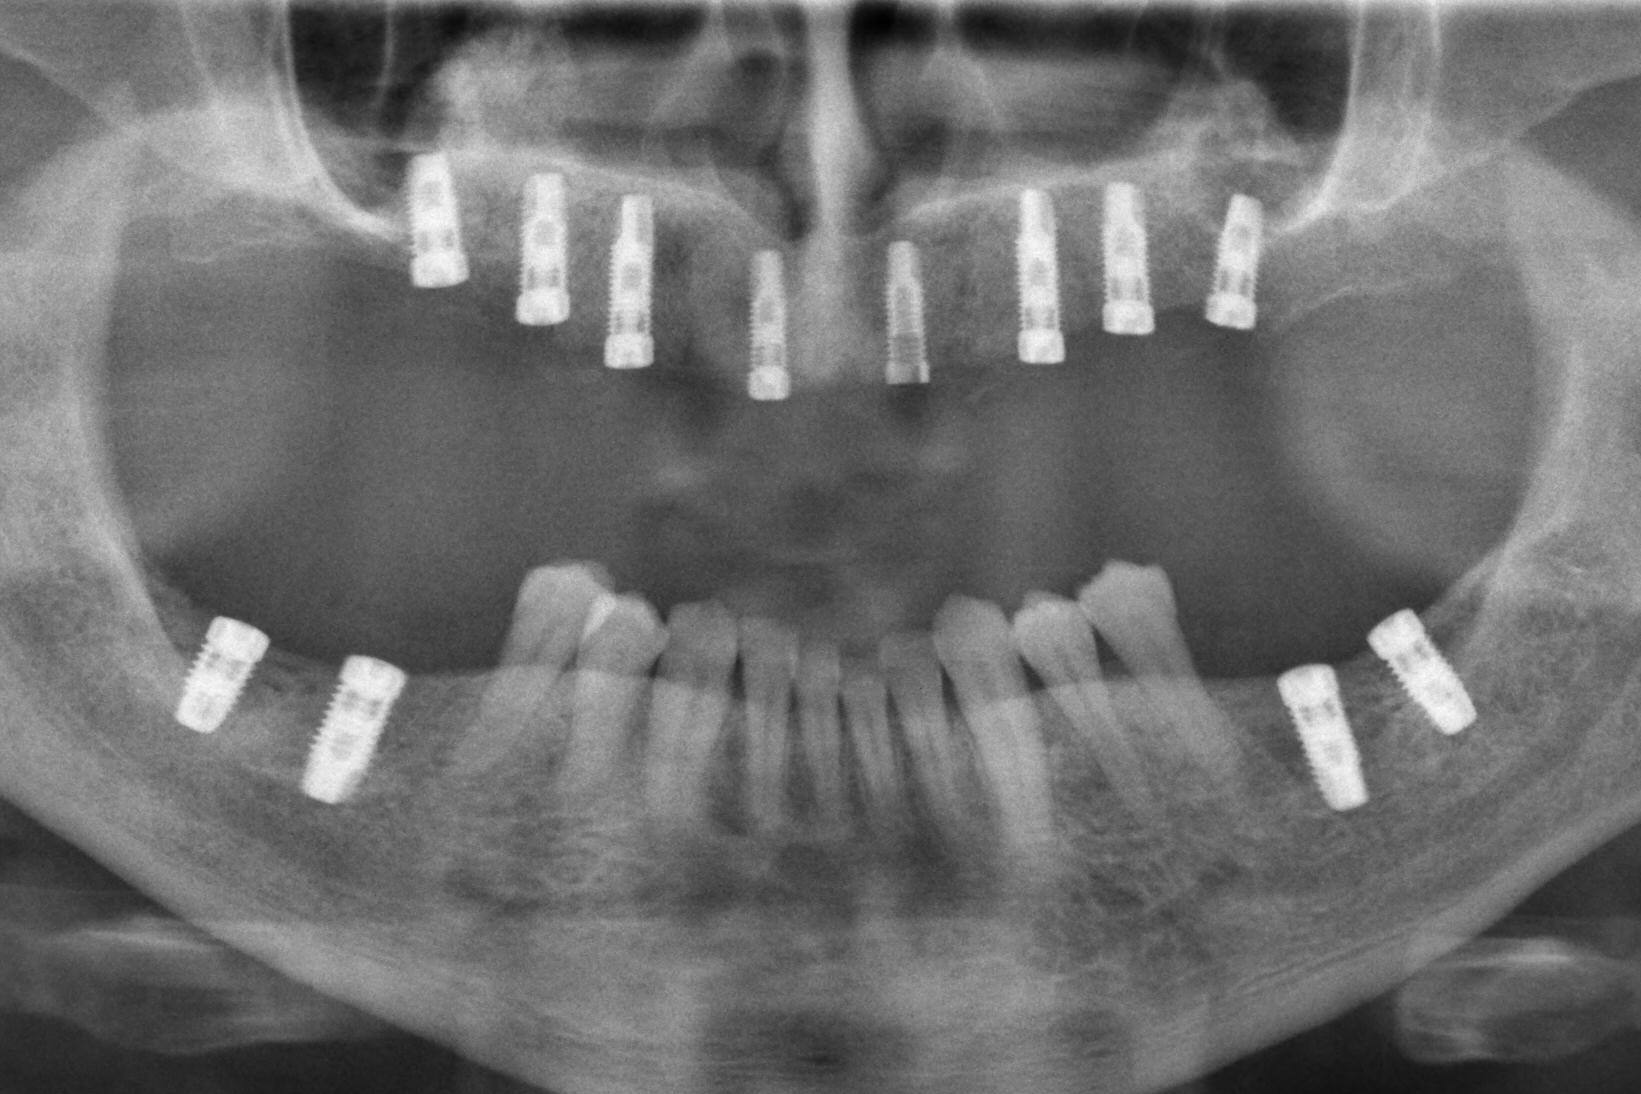

Bei unserer Sofortimplantat-Methode werden die hinteren Implantate meist schräg eingesetzt

und sofort mit den neuen Zähnen versorgt:

Durch die Schrägstellung sind einerseits längere Implantate möglich und andererseits werden gleichzeitig anatomisch wichtige Strukturen geschont (Unterkiefernerv, Kieferhöhle). Zusätzlich resultiert die Schrägstellung in einer statisch günstigeren Belastung und einer besseren Verteilung der Implantate (weiter hinten im Kiefer).

Vorher-Nachher-Röntgenbilder:

Ganzkiefer-Brücken auf 4 und mehr Implantaten